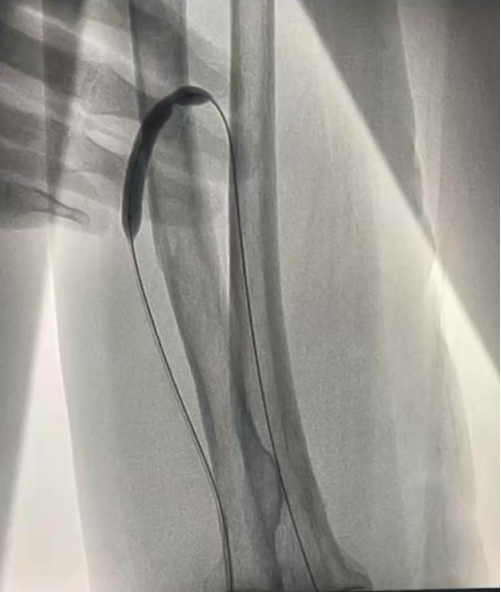

近日,在介入科大力协作和上级医院专家指导下,我院肾内科成功开展首例DSA引导下动静脉内瘘球囊扩张术(PTA under DSA guidance),顺利为透析患者打通“生命线”。

现年72岁的陆奶奶是外院一位靠血液透析维持生命的尿毒症患者,日前因左前臂人工内瘘功能不良再次前来我院就诊。入院后经查发现患者内瘘吻合口明显狭窄,进而导致内瘘功能不良,不能透析使用。患者高龄,为了保护和充分利用患者宝贵的血管资源,科室透析通路团队经过充分评估,决定对陆奶奶进行DSA引导下动静脉内瘘球囊扩张术。

经过充分沟通同意和术前积极准备,近日,在介入科协作和上级医院专家指导下,顺利经皮下穿刺患者动静脉内瘘,然后在DSA引导下将球囊送入血管的狭窄部分进行扩张。手术过程顺利,患者伤口小,痛苦轻,出血少。术后患者内瘘处听诊血管杂音清晰,可触及明显震颤,远心端血管充盈显著,超声评估内瘘吻合口血流量达标,手术十分成功。经过悉心指导进行内瘘功能锻炼和保护后,患者已于日前满意出院,回当地继续透析,同时科室密切随访。